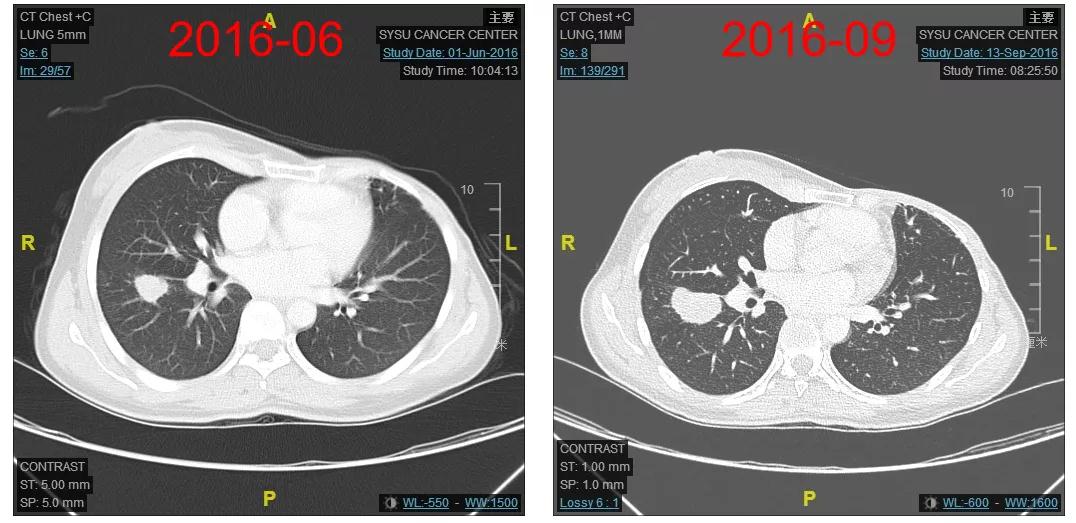

2016-06-01复查CT:右肺下叶上段团块状肿物(图1),考虑转移。

图1